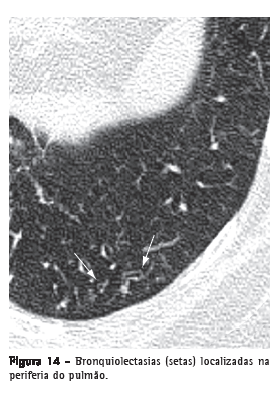

BronquiolectasiaDilatação bronquiolar. Análoga às bronquiectasias, mas em uma via aérea de muito menor calibre, identificada na periferia pulmonar (Figura 14). Manifestam-se como estruturas arredondadas ou tubulares, geralmente na periferia pulmonar, e com paredes espessadas ou preenchidas por secreção (ver Padrão de árvore em brotamento).(3,7) Também podem se associar a outras opacidades pulmonares e à distorção do parênquima em situações de fibrose.

Ver também Bronquiectasia e bronquiolectasia de tração.